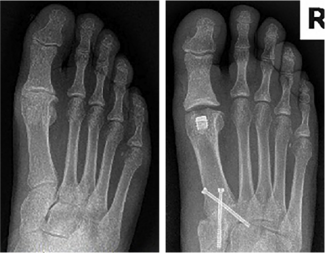

Daniel S. Schulman, DPM, FACFAS

The author reports a case of a 44-year-old male with painful hallux rigidus using a titanium hydroxyapatite-coated implant.